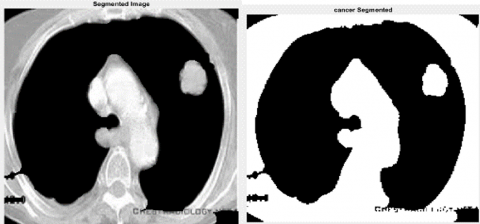

Region wrapping is the step of operations which eradicate incorrect boundaries and bogus regions by merging adjacent regions based on the gray value of these regions. Region wrapping is accomplished to group the tumor regions detected together as single layer of region after the thresholding. The complete segmentation results of each stage are illustrated in Figure 2.

(a) Original lungs image

(b) SLIC -Cancer segmented

(c) Optimal Thresholding (Enhanced image)

(d) Region Wrapping-abnormal malignant

Figure 2. Segmentation Results: a) Original Image; b) SLIC; c) Optimal Thresholding; d) Region Wrapping

In Figure 6, we shown the result of preprocessing stage, in which we used gamma correction-based image enhancement to improve the contrast of original image and that also clearly depicted in the above Figure 6. Next implementation is that segmentation of brainy region means removal of skull content available in the whole image as shown in Figure 7.

Once the gray segmentation output is obtained, we are performing pseudo color transformation using labelling method in morphological operations. This transformation will retain the highly infected regions if any in the segmented lungs cancer area. The output of segmented and pseudo color converted is illustrated in Figure 6.

Figure 6. Segmented image and pseudo color transformed image

Figure 6 shows the final result of lungs cancer detected content the classification results from our proposed method of ICCAN. Figure 7 is shown for the pictorial representation of performance comparison of our proposed with the existing algorithms of researches [28-31]. Table 1 is for numerical comparison.

Figure 6, shows the final result of tumor detected content the classification results from our proposed method of ICCAN.

Figure 7 is shown for the pictorial representation of performance comparison of our proposed with the existing algorithms of Stutz et al. [26, 27]. Table 1 is for numerical comparison the Table 1 is clearly shown that our proposed algorithm is provided the higher results than the existing methods of SVM and HMM. Different segmentation result and lungs cancer size of different category is depicted in Figure 7 below.